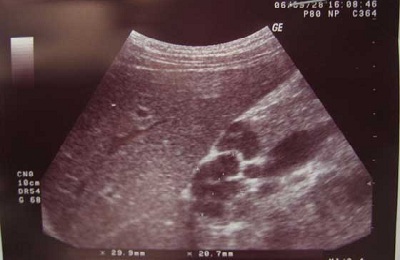

Во время процедуры обследования ультразвуковые волны проходят сквозь ткани легких и благодаря различию в их структурах, волны отражаются и улавливаются датчиком аппарата УЗИ. После того как данные обработаны, они передаются на экран аппарата, где специалист наблюдает их в виде черно-белой картинки.

После этого специалист составляет характеристику эхогенности. Длительность подобной процедуры составляет от десяти до двадцати минут. В этом случае все зависит от того, обнаружит ли врач патологии. А если таковых обнаружено не будет, пациент сразу узнает о благоприятном результате. Закончив обследование, специалист напишет для него заключение и приложит полученные снимки.

Плевральный выпот представляет собой накопление в полости плевры жидкости. Выпот – это водянистое образование, и поэтому при УЗИ он незаметен, но зато плевра хорошо показывает границы скопления жидкости, которые замечаются при дыхании пациента.

Определение жидкости, накопившейся в полости плевры, важно для результата диагностики. При исследовании метод сонографии не всегда эффективен, т.к. в транссудате нет веществ, способствующих его выявлению.

Ввиду этого подобный транссудат называют анэхогенным. По количеству этой жидкости судят о тяжести гипотериоза или цирротических очагах в печени. Скопление белков в экссудате дает шанс его заметить при обследовании ультразвуком.